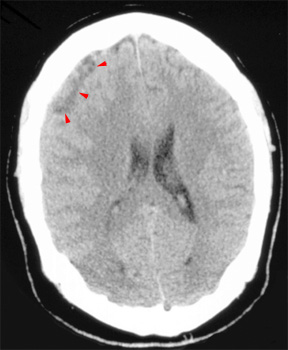

Head CT > Infection > Subdural Empyema

Subdural Empyema

Subdural

empyema is usually due to meningitis, sinusitis, trauma or prior surgery.

It is a neurosurgical emergency. Subdural empyema leads to rapid clinical

deterioration, especially if it is due to sinusitis. On CT it appears

as an isodense or hypodense extra-axial mass. It has a lentiform or crescentic

shape.

The margin of collection often enhances with contrast material administration

due to the presence of granulation tissue or subjacent cortical inflammation.

![]() Notice the heterogeneous subdural fluid collection.

In the same patient,